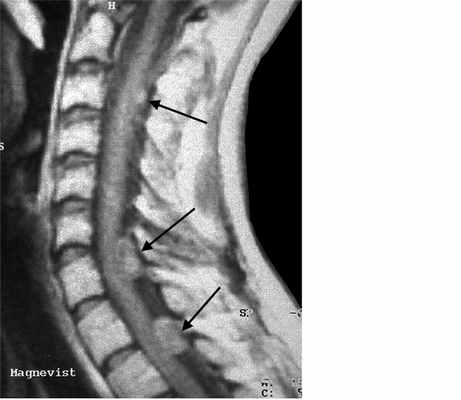

Невриномы (шванномы) и нейрофибромы составляют примерно половину опухолей этой локализации и 35% от всех спинальных опухолей. Гистологически невриномы происходят из шванновских клеток оболочек нерва (леммоцитов), прилегающих к заднему корешку. Обычно диагностируются они в возрасте 20 – 50 лет, у мужчин проявляются несколько в более молодом возрасте, чем у женщин. Они почти всегда одиночные, инкапсулированные, располагаются в любом отделе, но чуть чаще в поясничном или верхнем шейном. Множественные невриномы встречаются исключительно редко при нейрофиброматозе типа II. Нейрофибромы состоят из шванновских клеток и фибробластов, некоторые окружают задний корешок. Они почти всегда множественные и связаны с нейрофиброматозом типа I (болезнь Реклингхаузена). От 2 до 12% нейрофибром перерождаются злокачественно, превращаясь в нейрофибросаркомы. Несмотря на различие в гистологии характер роста опухолей одинаковый. Около 15% из них распространяются в экстрадуральное пространство через одно или несколько межпозвоночных отверстий, приобретая вид “песочных часов”. Такой тип роста особенно типичен для шейной локализации. На рентгенограммах рост по типу «песочных часов» может быть выявлен по расширению межпозвоночного ответстия и эрозии корня дуги. Клинические проявления неврином и нейрофибром состоят в радикулопатическом и миелопатическом синдромах.

На МРТ Т1-взвешенного типа и невриномы, и нейрофибромы изо- или слегка гипоинтенсивны по отношению к спинному мозгу. Однако, встречаются случаи и повышенного сигнала за счет сокращения Т1 мукополисахаридами, связанными с водой. Протонная плотность при МРТ повышена, а на Т2-взвешенных МРТ они чаще неоднородные, могут быть очень яркие участки, где имеется высокое содержание воды, и сравнительно низкого сигнала, особенно в центре. Обе опухоли хорошо контрастируются при МРТ. По форме невриномы округлые, границы ровные, четкие. Нейрофибромы вытянуты вдоль корешка, что лучше видно на корональных МРТ. Размеры могут быть самыми различными.

МРТ шейного отдела позвоночника. Нейрофиброматоз тип II. Множественные невриномы (стрелки). Т1-взвешенная МРТ с контрастированием.